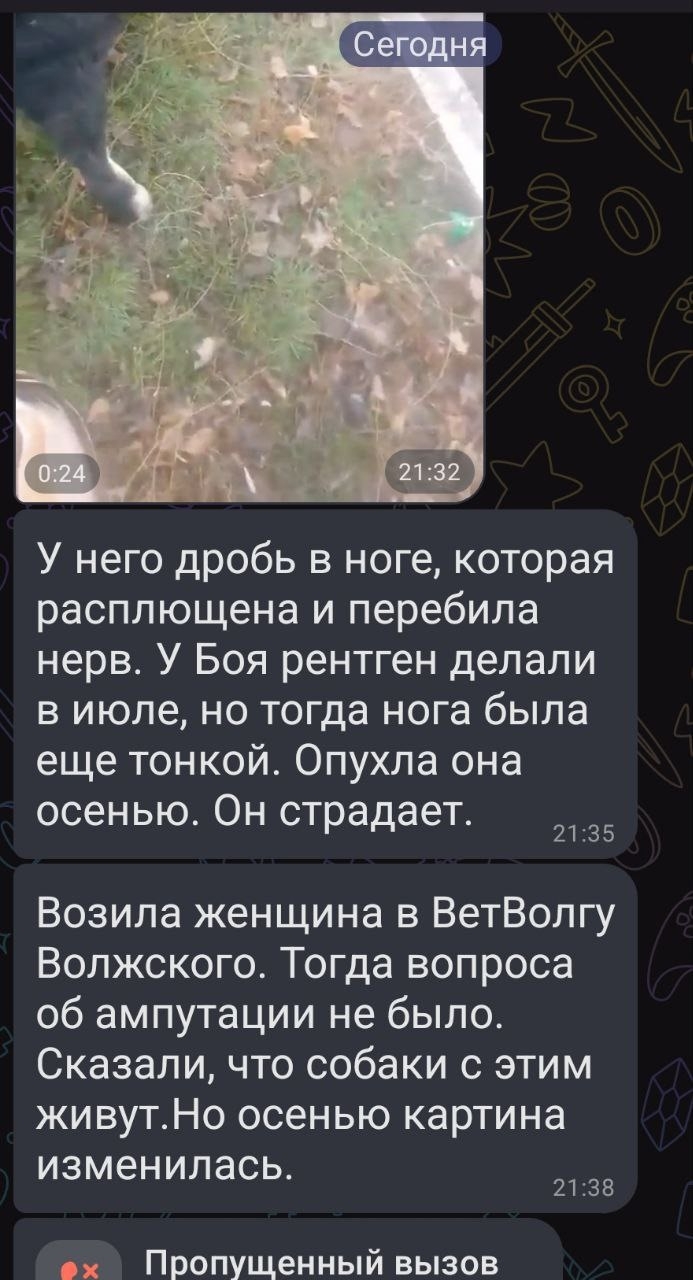

Бой — невероятно добрый и ранимый пес, но сейчас его жизнь превратилась в ад. Фото и видео были сделаны осенью, а сейчас ситуация катастрофическая: лапа распухла в разы, началась гангрена. Соседи говорят, что пес совсем плох — если не забрать его из этого гиблого места прямо сейчас, он умрет от сепсиса.

Когда-то Боя уже возили в Волгоград на рентген, но полноценного лечения он не получил и снова оказался на улице. Итог — инвалидность и гниющая заживо конечность.